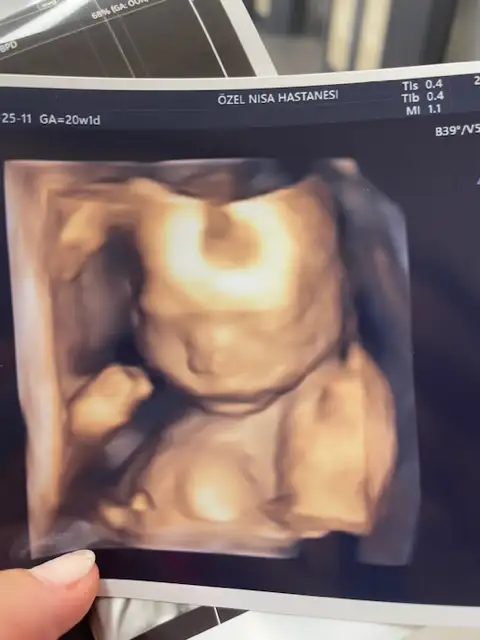

Ohh masallah kuzucukidrar yolu enf olmamışım yanlış görmüş aile hekimimgitmişken bi baktı doktor 400 gram 25 cm olmuş hanımefendi keyfimiz yerinde

Ay iyi hadi canımidrar yolu enf olmamışım yanlış görmüş aile hekimimgitmişken bi baktı doktor 400 gram 25 cm olmuş hanımefendi keyfimiz yerinde